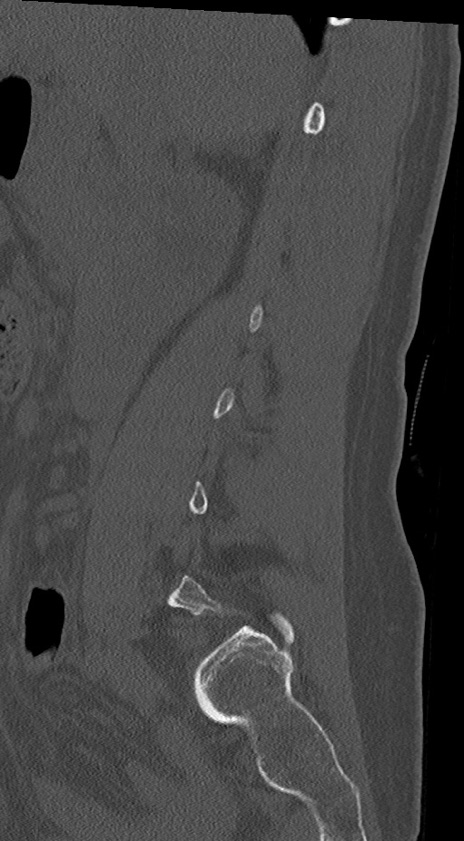

【整形】TIPS症例4 腰椎CT(矢状断像)

腰椎CT

冠状断像